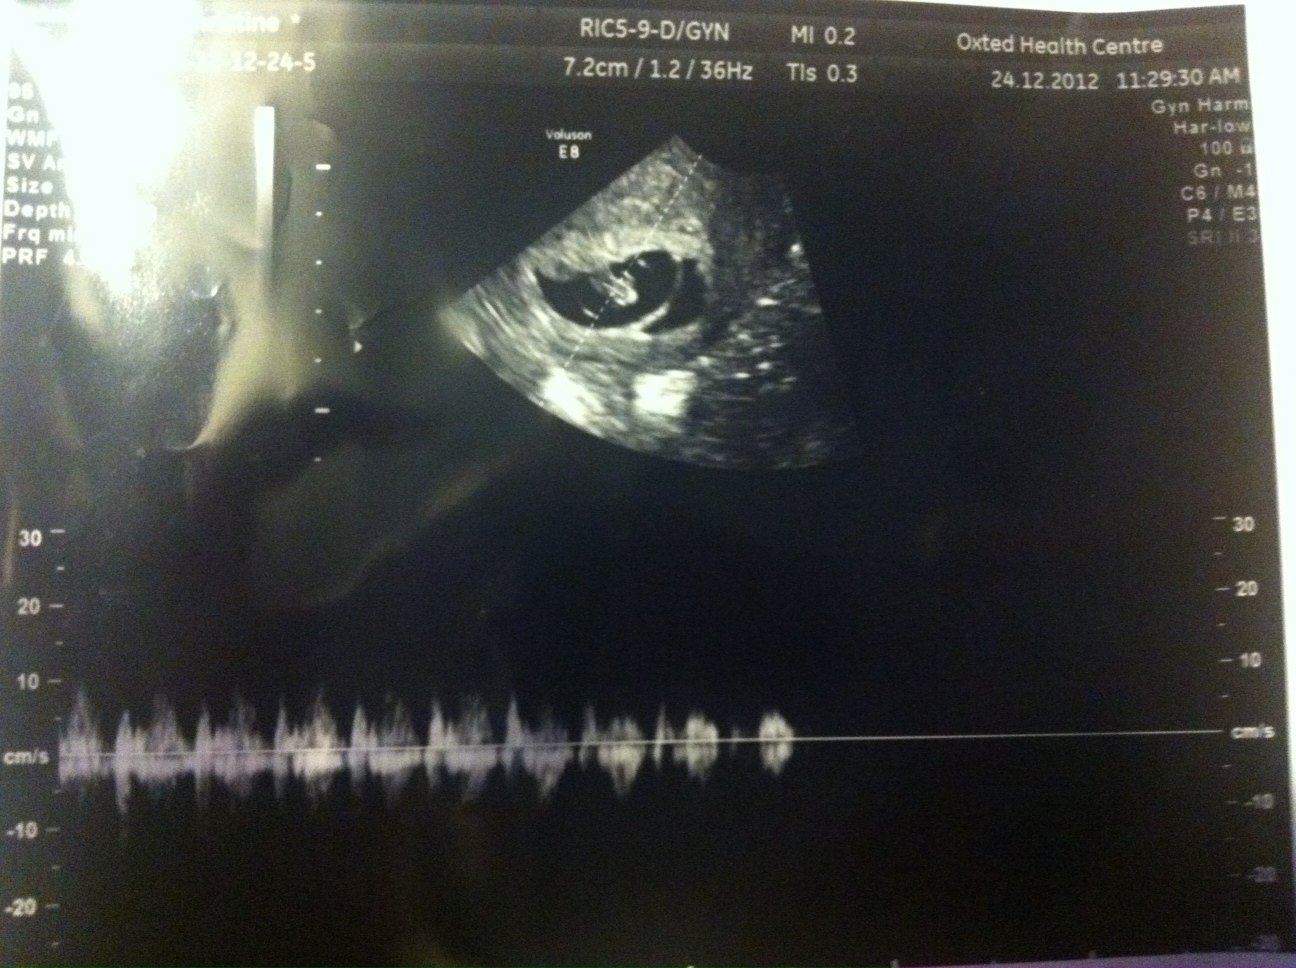

These are the pictures I got:

Attachment 7591

I then had a second (private) scan 6 days later and there were still 2 sacs yet this time it appeared there was a healthy baby in the big sac with yolk sac and heart beat and a CRL measurement of 13.8mm making it 7+5. The smaller sac still had an embryo and a tiny fetal pole but no heartbeat measured 3.6mm